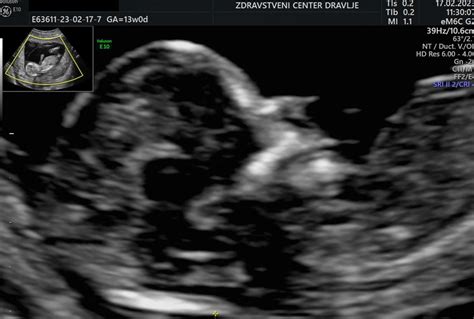

Nuhalna svetlina (NT - nuhalna translucenca) je v bistvu nakopičena tekočina v podkožju v predelu otrokovega vratu. V zgodnji nosečnosti, med 11. in 14. tednom, je ta tekočinski žep pri vseh plodovih prisoten. Vendar pa velikost tega žepa ni enaka pri vseh. Pri plodovih, ki imajo kromosomske napake, kot je na primer trisomija 21 (Downov sindrom), ali nekatere prirojene srčne napake, je ta nuhalna svetlina pogosto povečana. Zato merjenje tekočine v zatilju ploda predstavlja pomemben pokazatelj potencialnega tveganja.

Pregled nuhalne svetline je časovno omejen. Izvajamo ga lahko le med 11. tednom nosečnosti + 3 dnevi in 13. tednom nosečnosti + 6 dnevi. V tem obdobju je plod dovolj razvit, da je področje zatilja dobro vidno na ultrazvoku, hkrati pa je tekočinski žep še dovolj opredeljen, da ga je mogoče natančno izmeriti. Pregled se običajno izvaja skozi trebušno steno. Med postopkom se na trebuh nosečnice nanese poseben gel, ki omogoča jasnejše slike s pomočjo ultrazvočne sonde. Izkušeni ginekolog z veljavno licenco fundacije FMF (Fetal Medicine Foundation) uporabi visokofrekvenčne zvočne valove za pridobivanje slik otroka v maternici. Izmeri se debelina nuhalne svetline, ki se običajno giblje med 3 in 6 milimetri pri normalni nosečnosti.

- Velikost ploda (CRL - Crown-Rump Length): To je meritev od vrha glave do trtice, ki pomaga določiti starost ploda.